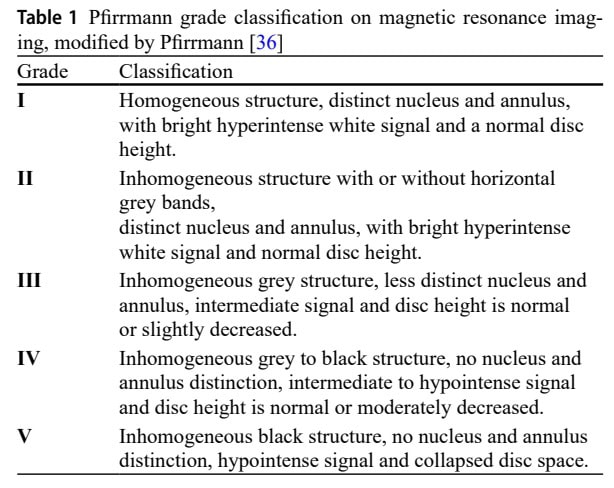

- Факторы пациента: Исходный уровень дегенерации (степень по Пфирману; суммарный балл по Пфирману), пол (мужской, женский) и индекс массы тела (ИМТ). Оценка по шкале Пфирмана - это система классификации для визуальной оценки степени дегенерации (IVD) с помощью МРТ. Она оценивает диски от одного (здоровые) до пяти (тяжелая дегенерация) на основании изменений в структуре IVD, различия между ядром и кольцом, яркости интенсивности сигнала и высоты диска. Оценка по шкале Пфирмана была одним из факторов пациента, использованных в исследовании для классификации исходного состояния IVD на подгруппы (нормальная, легкая, умеренная, тяжелая и прогрессирующая дегенерация) для анализа.